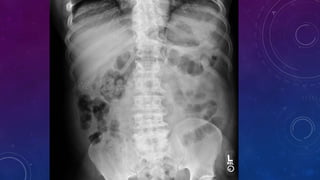

• Multiple pelvic phleboliths.

• Small well-defined round osseous lesions in the left

side of the abdomen, adjacent to midline represent

calcified lymph node in the para-aortic and left

common iliac groups, also visualized on the

corresponding CT.